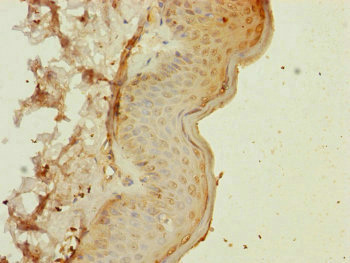

圖片:

應用范圍:ELISA, IHC

Application Recommended Dilution IHC 1:20-1:200 -